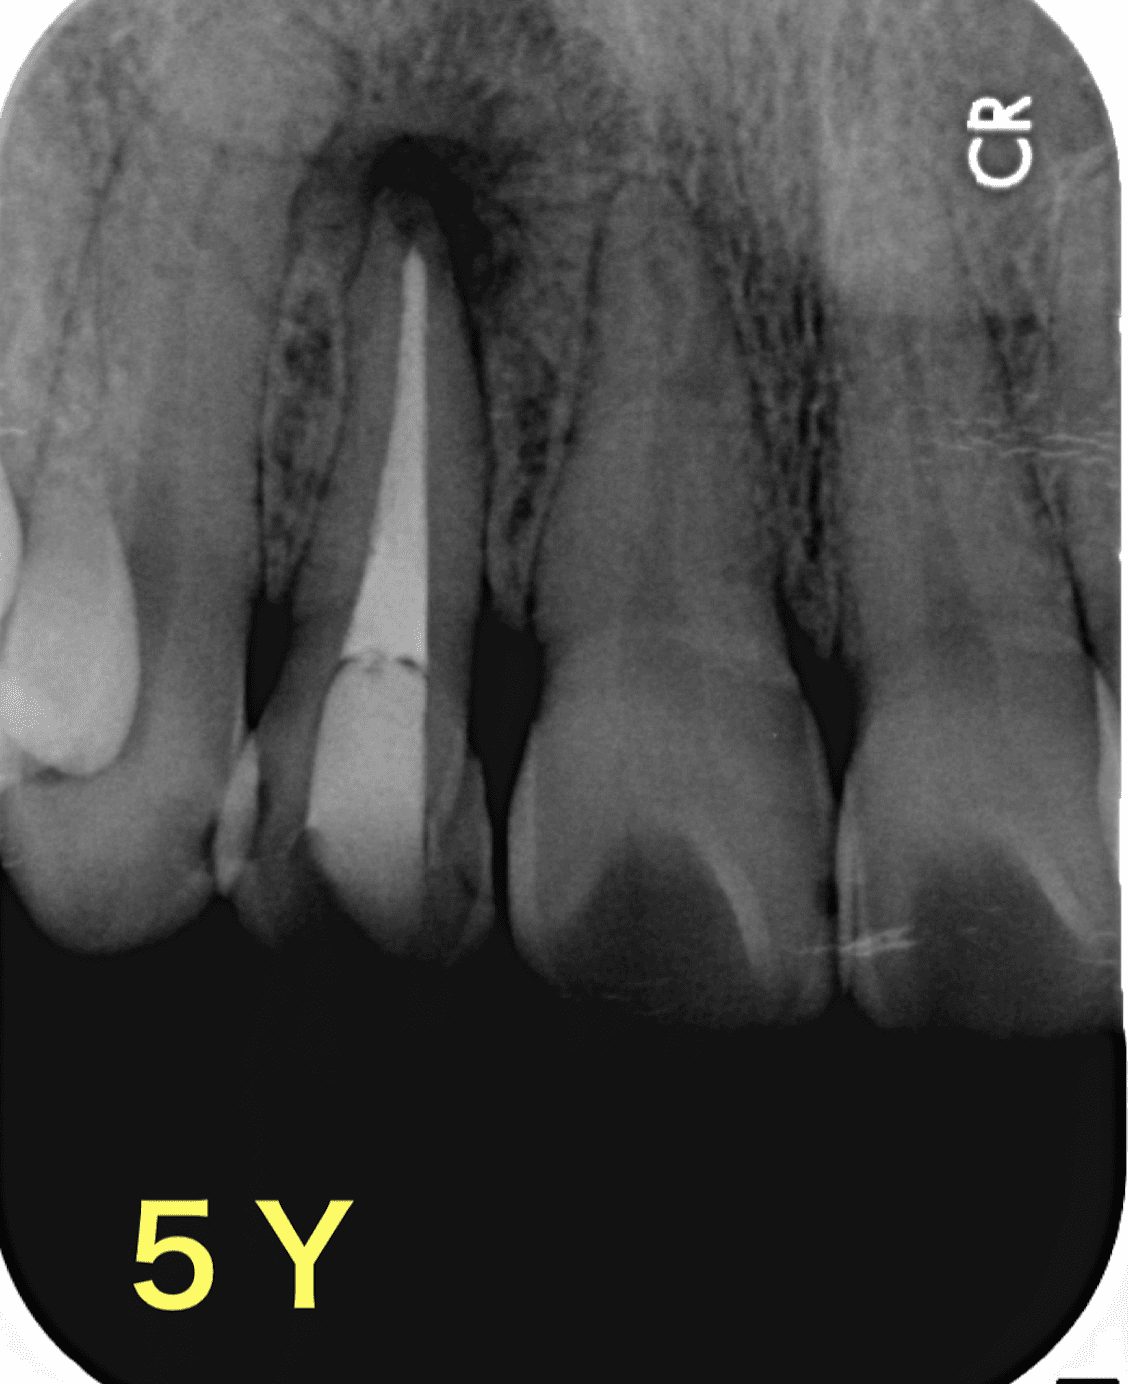

5年後

だいぶ病変が縮小しました。